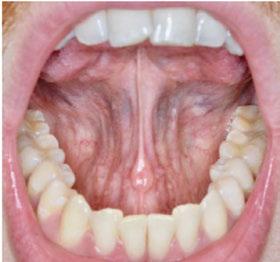

Upon closer examination, there were contributing factors that led to his discomfort. Stan had been a stomach/face sleeper for years. He also bit his nails since childhood, had a smoking habit from his youth, and he was prone to ear infections. He had moderate tongue and buccal ties, obligate mouth breathing, aggravated by a deviated septum, narrow nares, low tongue resting posture, an anterior open bite, a lower jaw that deviated upon opening, and bouts of acid reflux.

When the tongue rests in the palate, it impacts facial development especially for children who are still growing. An adult, for example, like our friend Stan, the progress made is gradual but more likely to last a lifetime. Generally, therapy starts out once a week for about 2-3 months. Then therapy progresses to every other week for 2-3 months, and then changes to once a month for about 5 months for the rest of the year. The exercises are done a minimum of 2 times everyday. These exercises are designed to strengthen and tone the orofacial muscles, building brand new neuromuscular function. When the muscles of the face are well developed, it may favorably impact appearance and the overall integrity of the facial structures. The muscles of the face also include the tongue, lips, cheeks and neck. Although the therapy program is typically only a year, Stan really liked how good he felt and decided to continue with some of the exercises to this day. From the photos you can see how much the program has impacted his health and well-being.

During his therapy, there was a discussion about the possible benefits he may receive from having his jaws expanded, making more room for his tongue, then to be followed by a tongue and buccal frenums release. His intermolar width is 34 mm, and his intercanine width is 25 mm. I feel any expansion has a potential benefit.

To document any initial assessment, the midpoint of therapy, and when therapy has ended, it is important to take detailed photos, videos, plus full measurements of the face and teeth. This makes it possible to compare results while showing that your therapy works based on the evidence you gathered before, during, and after treatment.

Figure 6: No room for his tongue

Figure 4: 7 years later on April 10, 2024. Anterior open bite closed a bit

Figure 2: Initial assessment on December 15, 2016 (top left). Later September 20, 2017, his anterior openbite widened (top right)